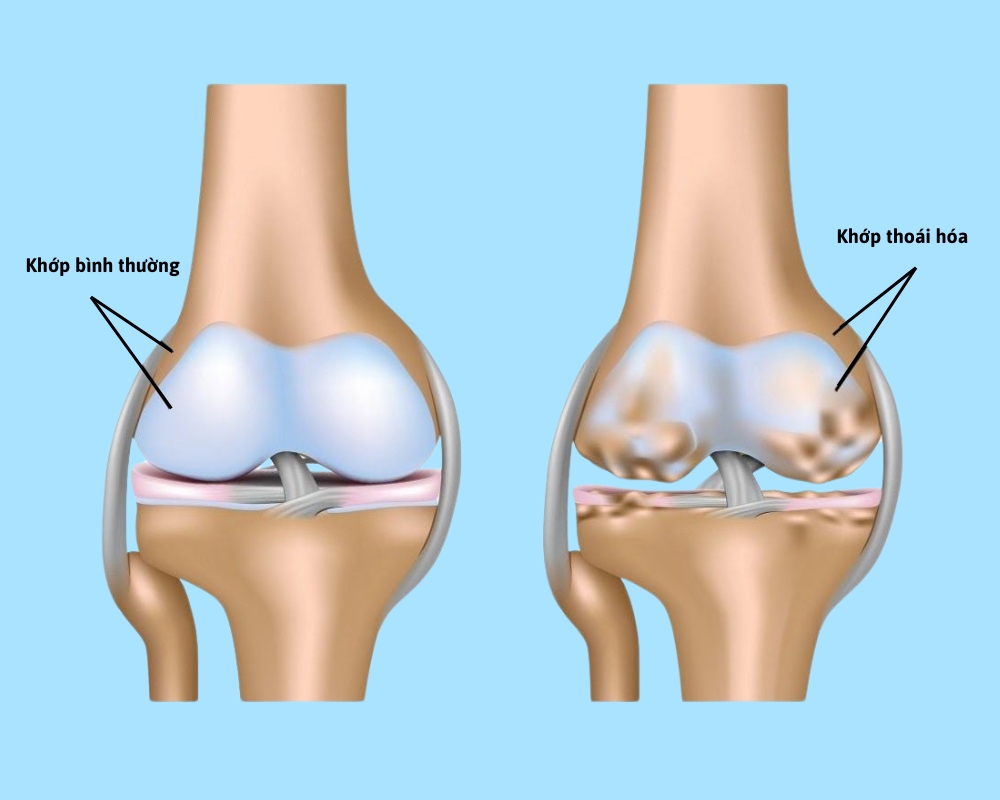

Thoái hóa khớp gối là một dạng phổ biến của viêm khớp. Thoái hóa khớp gối bao gồm những tổn thương trên bề mặt của sụn khớp, kèm theo phản ứng viêm và suy giảm dịch khớp. Do tác động của thời gian cùng nhiều nguyên nhân, sụn khớp dần bị mòn, mỏng và trở nên xù xì, không còn bảo vệ được đầu xương. Lúc này, những biến đổi ở bề mặt sụn khớp xảy ra, tăng lắng đọng canxi hình thành các gai xương, lâu dần các khớp bị biến dạng rồi hư khớp.

- Giai đoạn 2: Bạn sẽ dần cảm nhận được cơn đau sau một ngày dài vận động hoặc đi bộ, leo cầu thang, khớp bị cứng khi không vận động trong vài giờ hoặc lúc quỳ gối, cúi người. Lúc này, khi chụp X - quang, khoảng cách giữa các xương chưa bị thu hẹp và chưa bị cọ xát vào với nhau, dịch khớp còn đủ để vận động bình thường.

- Giai đoạn 3: Sụn bắt đầu có dấu hiệu tổn thương rõ ràng, khoảng cách giữa các xương bị thu hẹp. Người bệnh đau khớp thường xuyên khi vận động chạy, đi bộ, leo cầu thang, cúi… khớp cũng có thể cứng khi ngồi lâu và khi thức dậy sau một đêm. Tình trạng sưng khớp cũng có thể xảy ra trong giai đoạn này.

- Giai đoạn 4: Đây là giai đoạn thoái hóa khớp nghiêm trọng, người bệnh đau nhiều khi cử động. Khoảng cách giữa các xương bị thu hẹp, sụn khớp, xương dưới sụn bị hư tổn không còn nguyên vẹn, bị cọ xát vào nhau. Dịch khớp cũng ít đi và không còn khả năng giảm ma sát khi chuyển động.